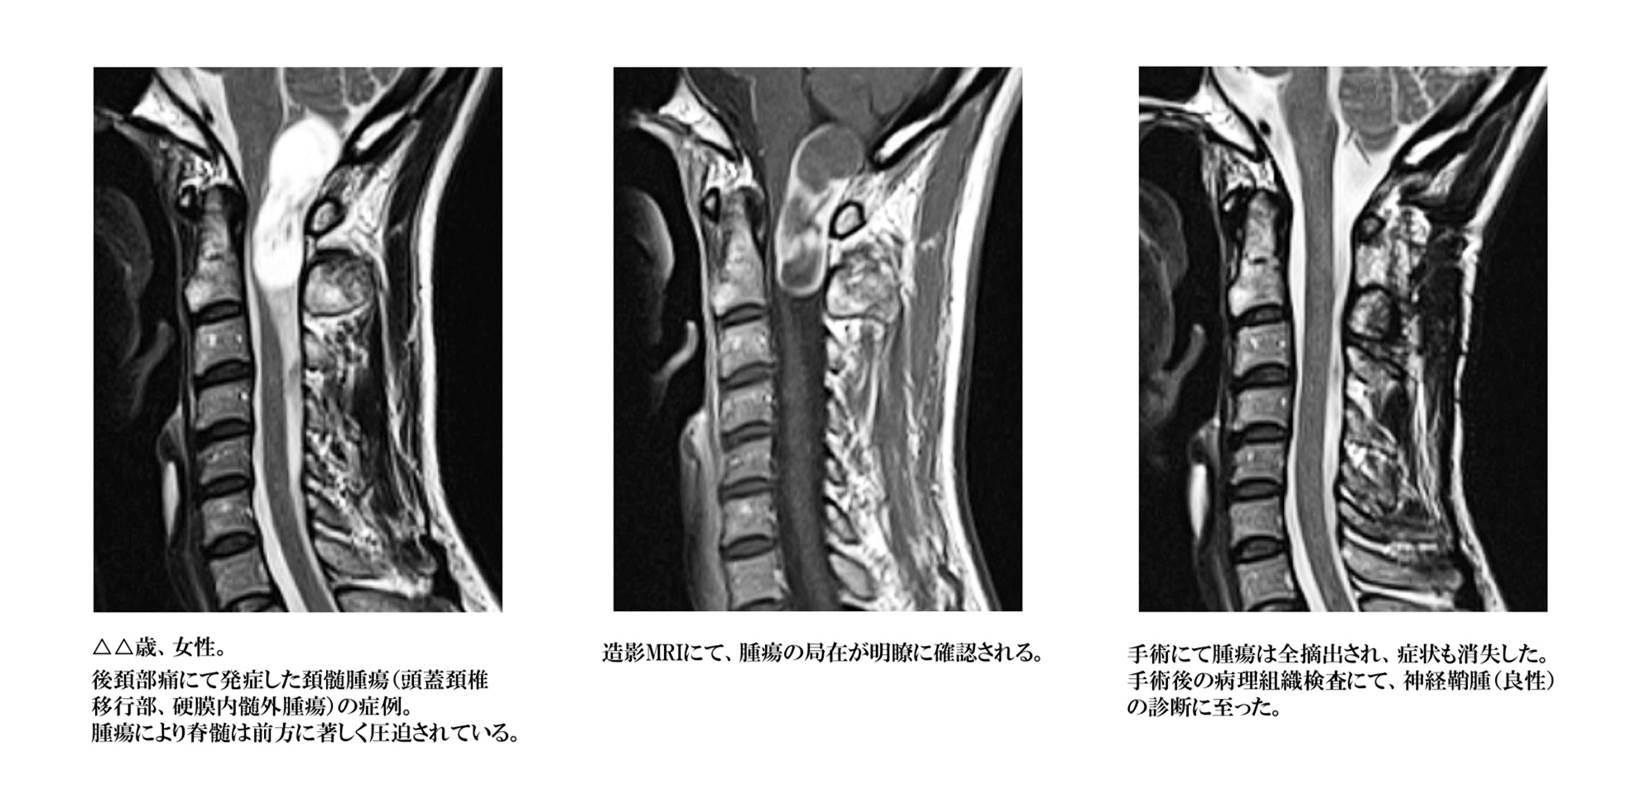

脊髄腫瘍

脊髄・神経・血管に由来する腫瘍性病変の総称であり、発生母地、存在部位、悪性度などにより種々の種類が存在します。脊髄の内部に存在する脊髄髄内腫瘍、脊髄を包んでいる硬膜の内側で脊髄の外側に存在する硬膜内髄外腫瘍、硬膜の外側に存在する硬膜外腫瘍などに分類されます。

硬膜内髄外腫瘍

脊髄神経の神経線維の再外側に存在する膜様組織である神経鞘から発生する神経鞘腫、脊髄を包んでいる硬膜から発生する髄膜腫の2種類で大部分が占められます。

いずれの腫瘍も、良性で全摘出ができれば治癒が得られますが、腫瘍の存在部位などによって全摘出できない場合、悪性腫瘍の場合などでは治癒を得る事が困難となります。腫瘍の種類、残存腫瘍の程度、症状の程度などによって追加の治療が必要になります。

摘出術

病変そのものを取り除く手術方法です。背骨は身体の深いところに位置していますので、病変を摘出するにも前述した減圧術に準じた手術操作を併用する必要があります。脊髄腫瘍など脊髄、神経自体にできた病変を取り除く場合と、大きく脊柱管内に脱出した椎間板ヘルニアや脊椎腫瘍、腫瘤などの骨、靱帯などにできた病変を取り除く場合があり、手術の危険性、手術による後遺障害などに大きく影響します。